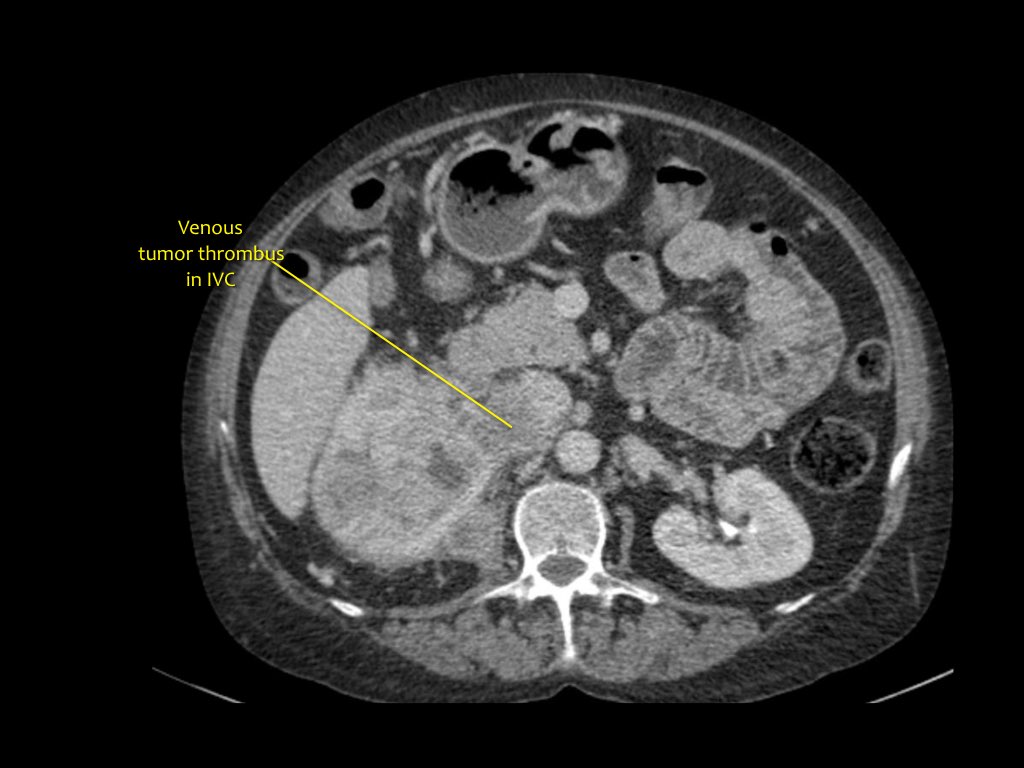

Phân giai đoạn RCC

RCC có thể xâm lấn mỡ quanh thận vượt qua cân thận và có thể lan vào tĩnh mạch thận, tĩnh mạch chủ dưới (IVC) hoặc tuyến thượng thận cùng bên.

Đối với phẫu thuật viên, điều quan trọng là cần biết có huyết khối u trong IVC hay không và liệu huyết khối có lan vào lồng ngực trên cơ hoành hay không (cần có phẫu thuật viên lồng ngực trong ca mổ).